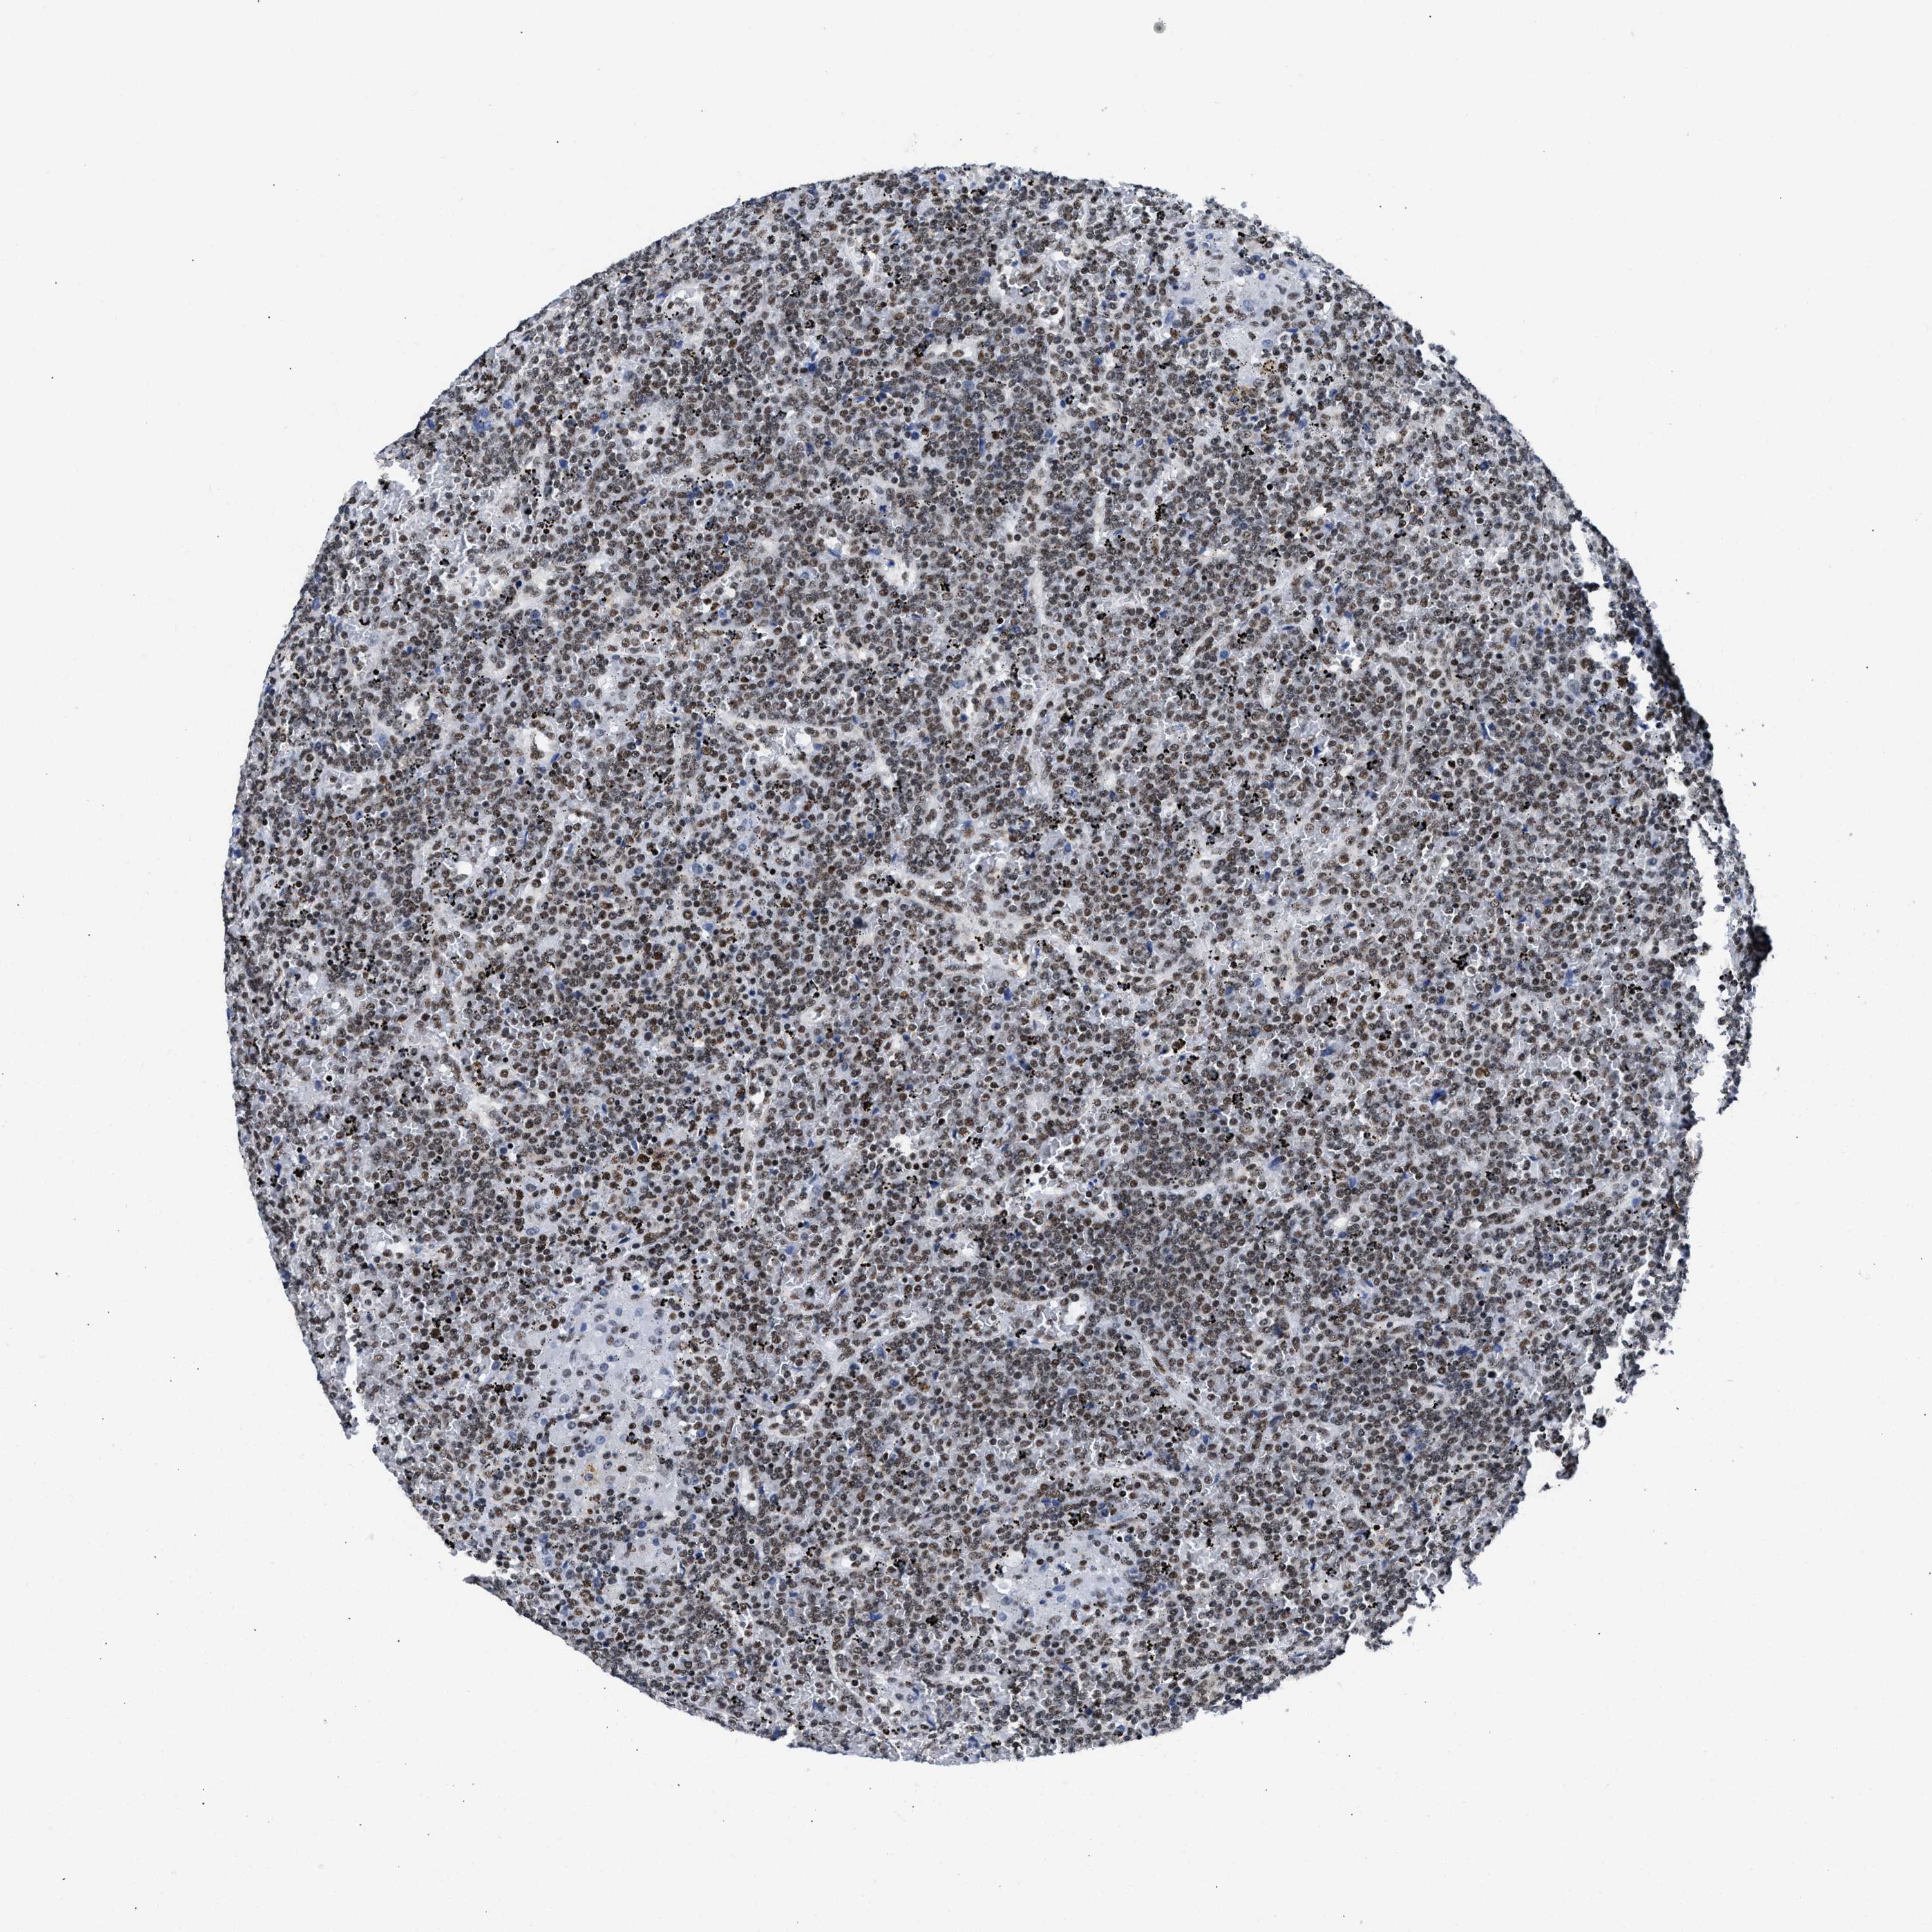

CANCER LYMPHOMA Show tissue menu

LYMPHOMA - Protein expressioni

A mouse-over function shows sample information and annotation data. Click on an image to view it in a full screen mode. Samples can be filtered based on level of antibody staining by selecting one or several of the following categories: high, medium, low and not detected. The assay and annotation is described here.

Antibody stainingi

Antibody staining in the annotated cell types in the current human tissue is reported as not detected, low, medium, or high, based on conventional immunohistochemistry profiling in selected tissues. This score is based on the combination of the staining intensity and fraction of stained cells.

Each image is clickable and will lead to virtual microscopy that enables deeper exploration of all samples and also displays staining intensity scores, fraction scores and subcellular localization as well as patient and tissue information for each sample.

Antibody HPA018403

Staining

Medium

Intensity

Moderate

Quantity

75%-25%

Location

Nuclear

Hodgkin's disease, NOS

Malignant lymphoma, non-Hodgkin's type, High grade

Malignant lymphoma, non-Hodgkin's type, Low grade